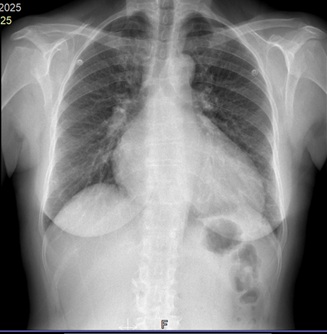

• Pruebas complementarias: En analítica sanguínea se objetiva proBNP elevado (4527 pg/ml), resto de analítica sin alteraciones. En radiografía de tórax se aprecia cardiomegalia. En ECG, bloqueo de rama izquierda.